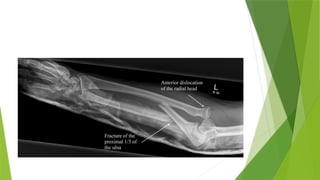

MONTEGGIA FRACTURE;DISLOCATION OF

THE ULNAR

 Previously this described a fracture of the shaft of the ulna associated with dislocation of the proximal

radio-ulnar joint.The radiocapitellar joint is inevitably dislocated or subluxated as well

 Recently it also entails any fractures of the ulna associated with dislocation of the radio-capitellar joint.

 If the ulnar shaft fracture is angulated with the apex anterior then the radial head is displaced anterior

 If the ulnar shaft fracture apex is posterior the radial head dislocation is posterior

 If the fracture apex is lateral then the radial head is displaced laterally.

MONTEGGIA FRACTURE;DISLOCATION OF THEULNAR  Previously this described a fracture of the shaft of the ulna associated with dislocation of the proximal radio-ulnar joint.The radiocapitellar joint is inevitably dislocated or subluxated as well  Recently it also entails any fractures of the ulna associated with dislocation of the radio-capitellar joint.  If the ulnar shaft fracture is angulated with the apex anterior then the radial head is displaced anterior  If the ulnar shaft fracture apex is posterior the radial head dislocation is posterior  If the fracture apex is lateral then the radial head is displaced laterally.  In children the ulnar injury maybe an incomplete fracture called greenstick or plastic deformation of the shaft  MOA;Usually the cause is the fall on the hand if at the moment of impact the body is twisting its momentum may forceably pronate the forearm.Somtimes the causual force is hyper-extension  CLINICAL FEATURES; The ulnar deformity is usually obvious but the dislocated head of radius is masked by swelling .A usueful clue is pain and tenderness in the lateral side of the elbow.The wrist and hand should be eamined for signs of injury to the radial nerve